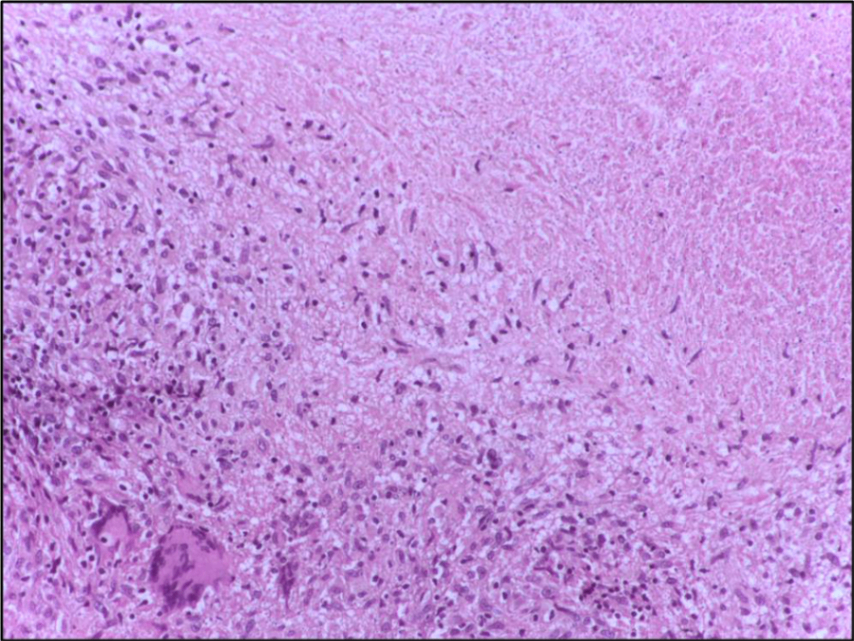

건락괴사(Caseous) | • 만성 육아종성 염증에 의한 괴사 • 대식세포 중심 면역반응 (Th1, IFN-γ 등) | • 연한 백색 치즈같은 괴사물 • 주위에 육아종: epithelioid cell + multinucleated giant cells | •결핵(TB) • 히스토플라스마증 등 일부 진균 감염 |

Tuberculous lymph node with caseating granuloma 40X, Wikimedia Commons